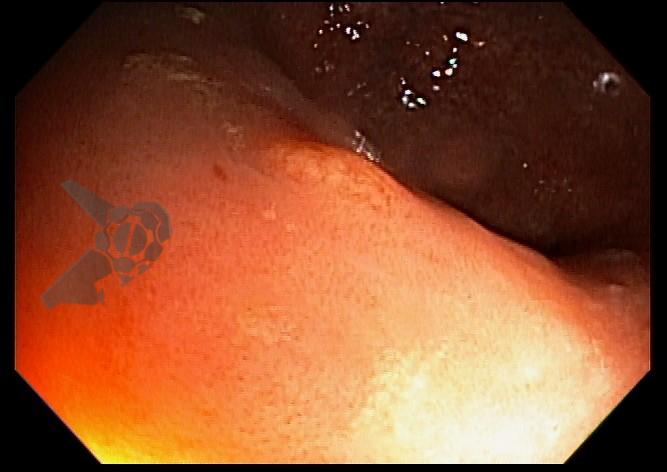

Paciente veio encaminhado para realizar nova colonoscopia na tentativa de ressecção completa da lesão. Durante o procedimento foi observada uma diminuta lesão amarelada no reto, discretamente elevada, correspondente à área de polipectomia prévia com presença de lesão residual (Figuras 1, 2 e 3). Realizada tentativa de mucosectomia pela técnica de imersão (“underwater”), não havendo pega adequada com a alça para ressecção. Foi optado, então, pela realização da mucosectomia por imersão assistida por cap, que consiste na imersão do espaço intraluminal com água, seguido por sucção da lesão com auxílio de cap endoscópico, afim de formar um pseudopólipo, e assim facilitar a apreensão e ressecção da lesão (Figura 4). Com o uso dessa técnica foi possível apreender a lesão residual com a alça e realizar sua ressecção completa (Figuras 5 e 6). O resultado anatomopatológico confirmou a presença de tumor neuroendócrino bem diferenciado (grau 1 – Ki67<2%), com margens laterais e profunda livres.